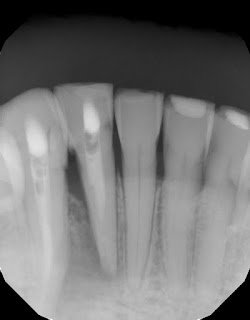

Sometimes we are quick to assume a tooth is fractured when we see lateral bone loss. But that radiographic finding alone isn’t enough to make that determination. If you cannot visualize a fractured, and the tooth is diagnosed as a necrotic pulp, it doesn’t matter how big the lucency is, it can and should be given the opportunity to heal. Proper diagnosis to determine vitality is the most important test for the prognosis of this tooth. In this case, with definite necrotic pulps on #26 and #27 and no periodontal defects, endodontic therapy is recommended.

Necrotic pulp with sinus tract on the buccal of #26.

CBCT shows the apical and lateral bone loss on #26 and #27. The lateral bone loss on #27 is also suggestive of a possible root fracture, but since the tooth is necrotic, radiographic appearance alone is not enough evidence to diagnose this with a root fracture. CBCT also shows a 2 canaled root form on #26.